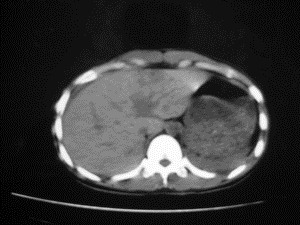

患者女,20岁,被车撞伤3小时,pe:全腹肌紧张,压痛反跳痛,以右上腹为著,肠鸣音减弱。有手术结果。![]() ![]() ![]() ![]() ![]() ![]() ![]() ![]() ![]() ![]() ![]() ![]() ![]() ![]() ![]() ![]() ![]() ![]() ![]() ![]() ![]() jiajie发言: ![]() 考虑空腔脏器穿孔。 dyqct发言:考虑:1、肝左叶外侧段断裂伤伴少量腹血。2、空腔脏器穿孔。 fangzheng发言:仅见腹腔内游离气体,提示空腔脏器穿孔。 guoke发言:胃内密度增高,肠腔内充满气体,考虑肠腔破裂出血 mmg94发言:胃后壁见一增厚软组织密度影,肝左叶前见游离气体影,左腹腔内局部肠管壁、系膜增厚。并见类圆形软组织。以上征象提示消化道管腔破裂,小肠、肠系膜挫裂伤,腹腔血肿形成。 拾荒者发言:肝实质密度不均匀,胃内见不均匀高密度影。考虑:肝挫裂伤,胃内应激性溃疡出血。 守望可可西里发言: 以下是引用jiajie在2006-6-20 15:49:00的发言:[br] [br][br]考虑空腔脏器穿孔。jiajie老师,我鼓起了很大的勇气才决定给您唱个反调儿,如果我错了,请您一定给我指出来,谢谢您了。我反复看了解剖图谱,觉得您所说的“考虑空腔脏器穿孔”上图所用箭头标明的不是游离气体。请您看以下几幅图片: ![]() ![]() ![]() ![]() ![]() ![]() ![]() ![]() 再请您看向医生老师发表的解剖图谱3幅 ![]() ![]() ![]() 这以下几幅图,我认为是肝包膜下积血。不过,说实在话,我没有发现有明显的肝挫裂伤。不对的地方请您一定指出来,再次感谢您了,jiajie 老师! ![]() ![]() ![]() ![]() 这下面几幅图片,我认为有明显的左中上腹部小肠损伤。 ![]() ![]() ![]() ![]() ![]() ![]() ![]() ![]() jiajie 老师,估计我说的是错误的,但我实在闹不明白,请您一定不要笑话我,并指出我的错误,以便于我减少工作中的失误。再次感谢您了,jiajie 老师! 至于胃内的不均匀高密度,我认为拾荒者战友说的有道理,胃内应激性溃疡出血和胃内容物混合所致。 手术结果:左肝叶(iv段)前缘长约8cm挫裂伤口,舌叶根部下< |